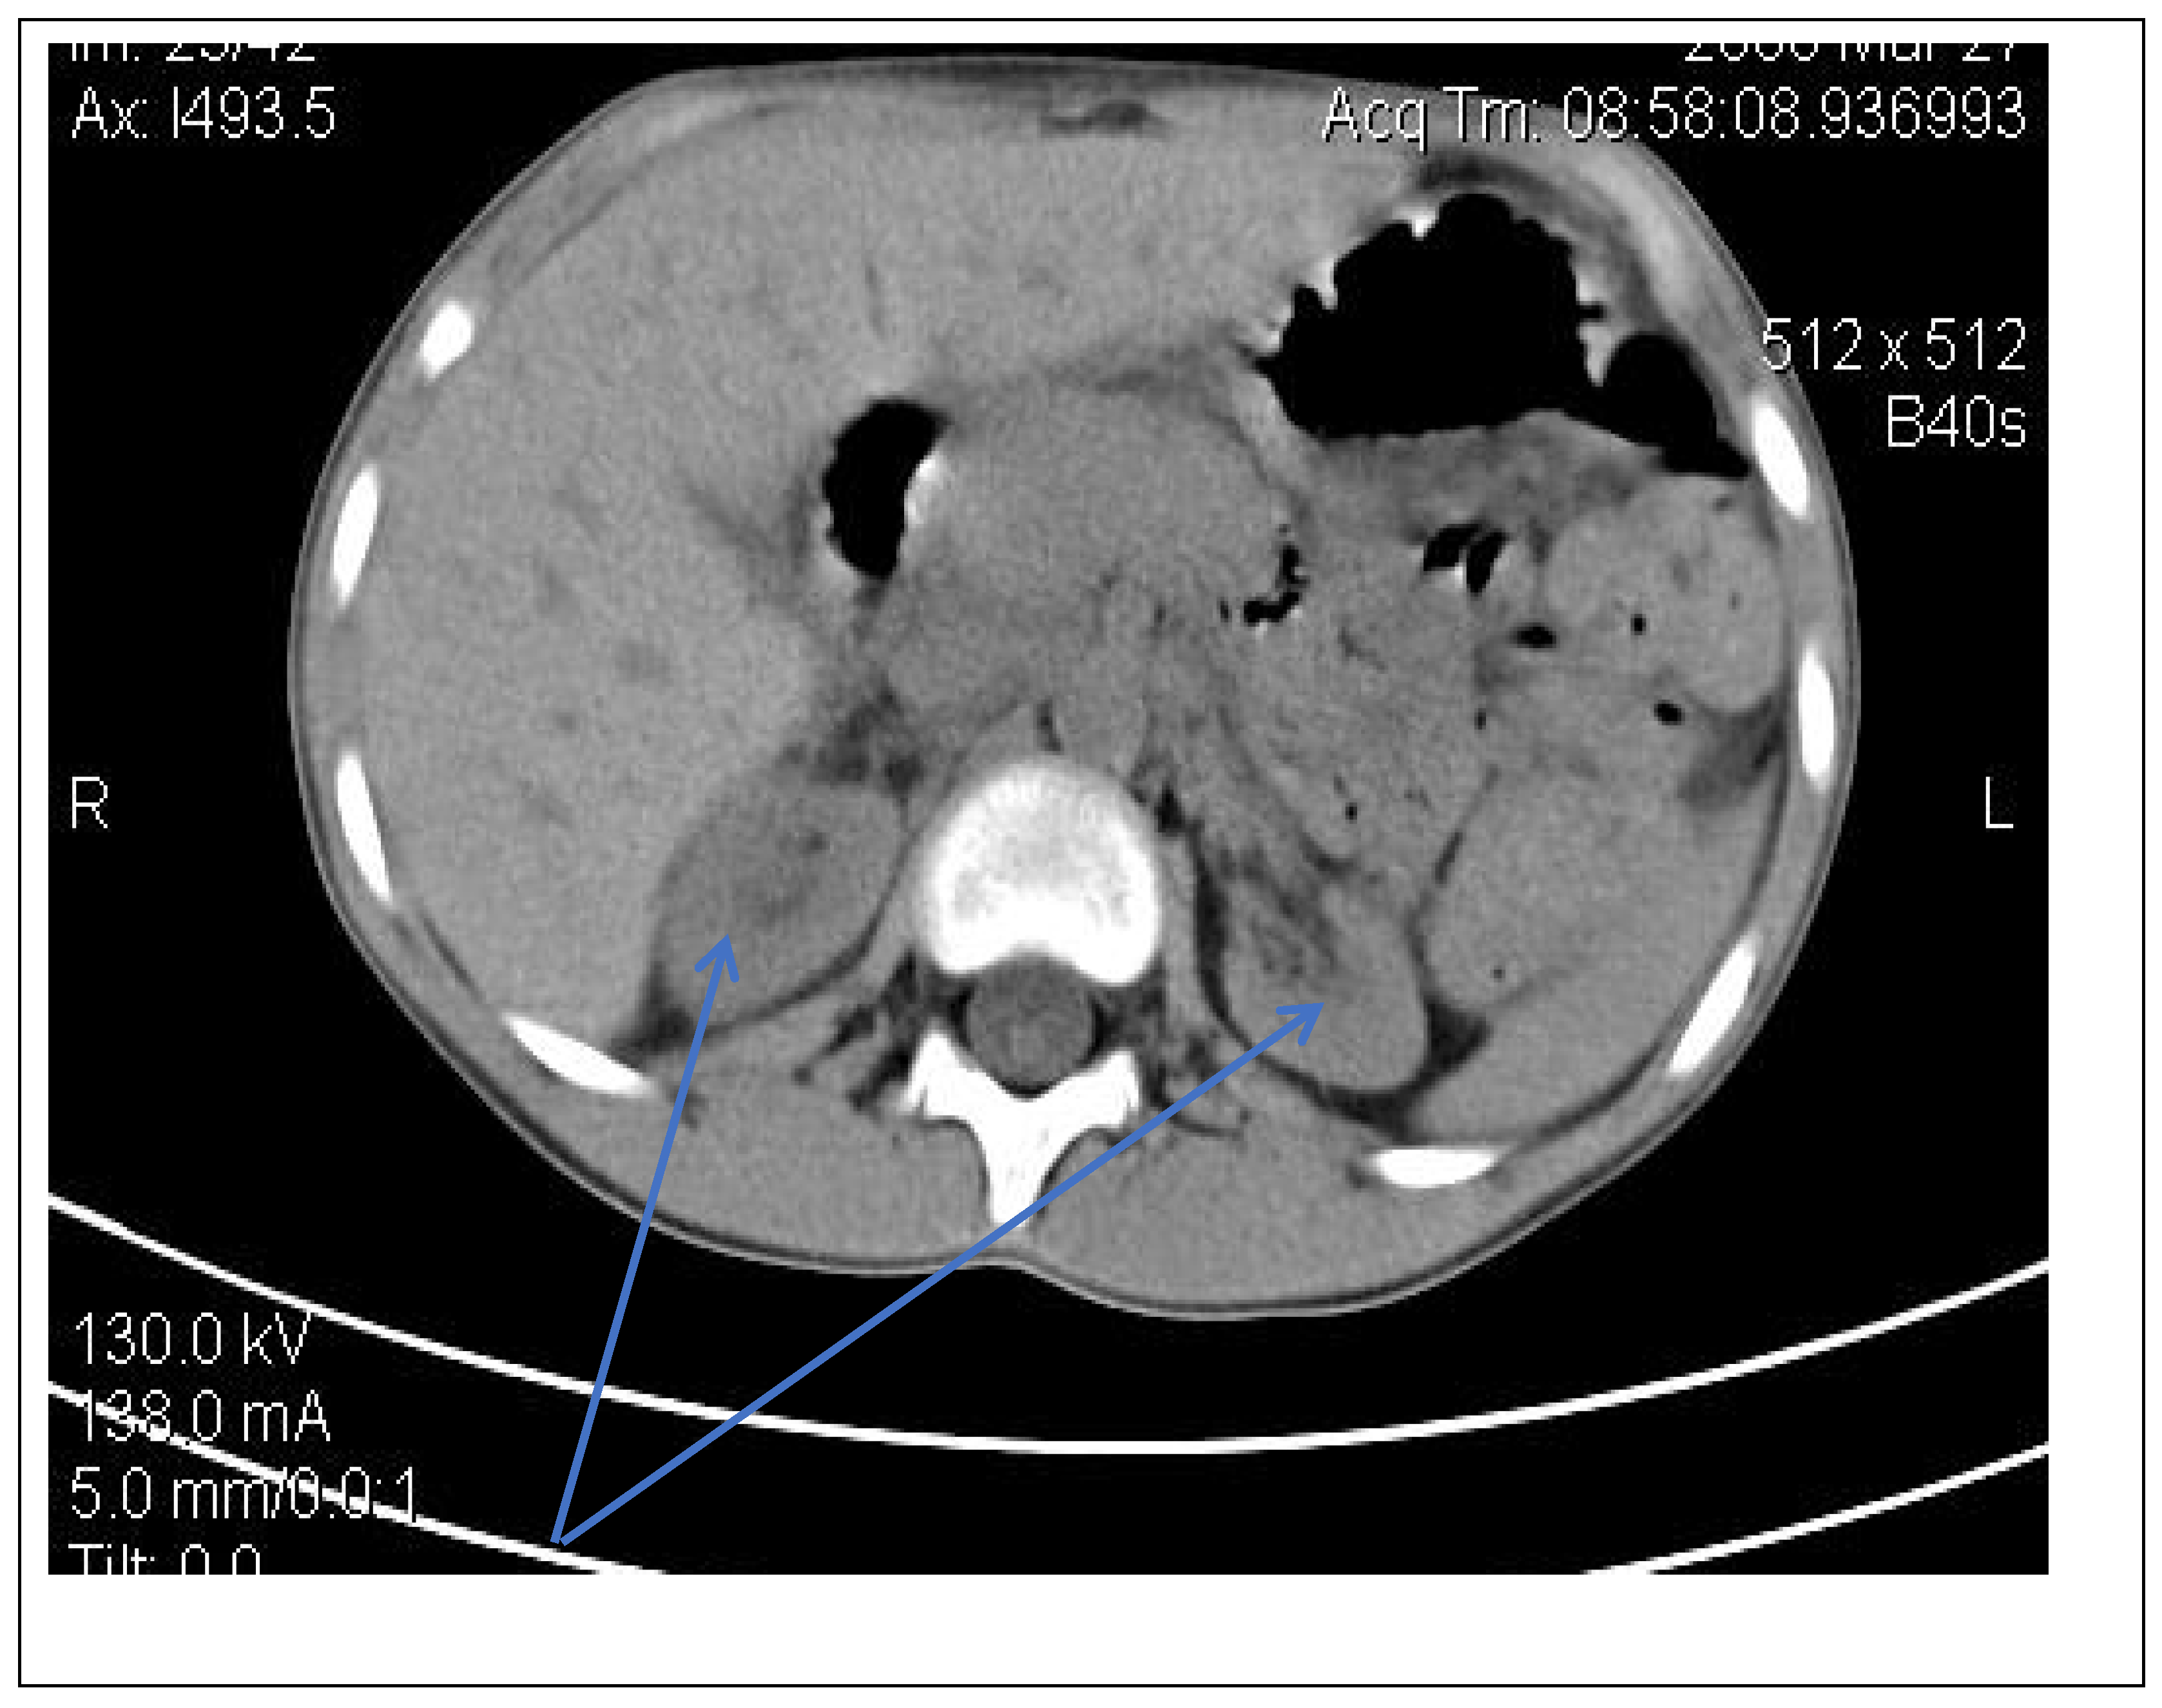

Abdominal-pelvic computed tomography with contrast substance (Figure 2)

delayed and symmetrically reduced renal secretion

are described expansive renal formations replacing renal parenchyma and with a mass effect on it

Figure 2. Abdominal CT scan—expansive renal formations replacing renal parenchyma and with a mass effect (blue arrow).

Following the evaluations for the etiology of end stage renal disease (ESRD) we recommended abdominal ultrasound and CT scan. The abdominal ultrasound showed multiple homogenous hyperechoic nodular formations. The CT scan showed expansive renal formations replacing renal parenchyma, with a mass effect on it (Figure 2). We thought in that moment of a bilateral nephroblastoma, but the clinical and biological dates excluded it. There remained a possibility of extrapulmonary renal tuberculosis (due to his personal and family history). Even if the culture was negative for Koch Bacillus, while a value of 22 mm Palmer III—suggests tuberculin turn, the treatment was initiated according to the international guidelines [6] by the phthisiologist: triple combination of isoniazid, rifampicin and pyrazinamide in doses adjusted to his clearance, in the 7/7 scheme for 2 months, then isoniazid and rifampicin in the same doses 7/7 for another 7 months [6]. Two months after the initiation of the tuberculostatic treatment, a CT reevaluation was performed, which showed no changes in the renal formations, although biologically the inflammatory syndrome was absent. The child continued the chronic dialysis program and still had important palm-plant pain burning type. The suspicion of chronic glomerulonephritis with evolution towards end-stage renal failure remained, so, we decided to perform the kidney biopsy who showed Chronic glomerulonephritis with segmental and diffuse glomerular hyalinization (Table 1, Figure 3, Figure 4, Figure 5 and Figure 6).